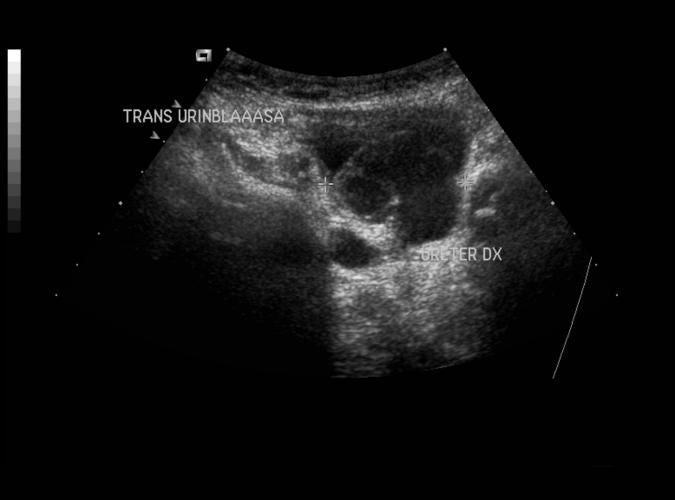

av Catherine Olsson, sonograf

Patologi.

Long höger njure. Nyfödd med dubbla njurbäcken med dilatation av övre systemet.. se bild 9h